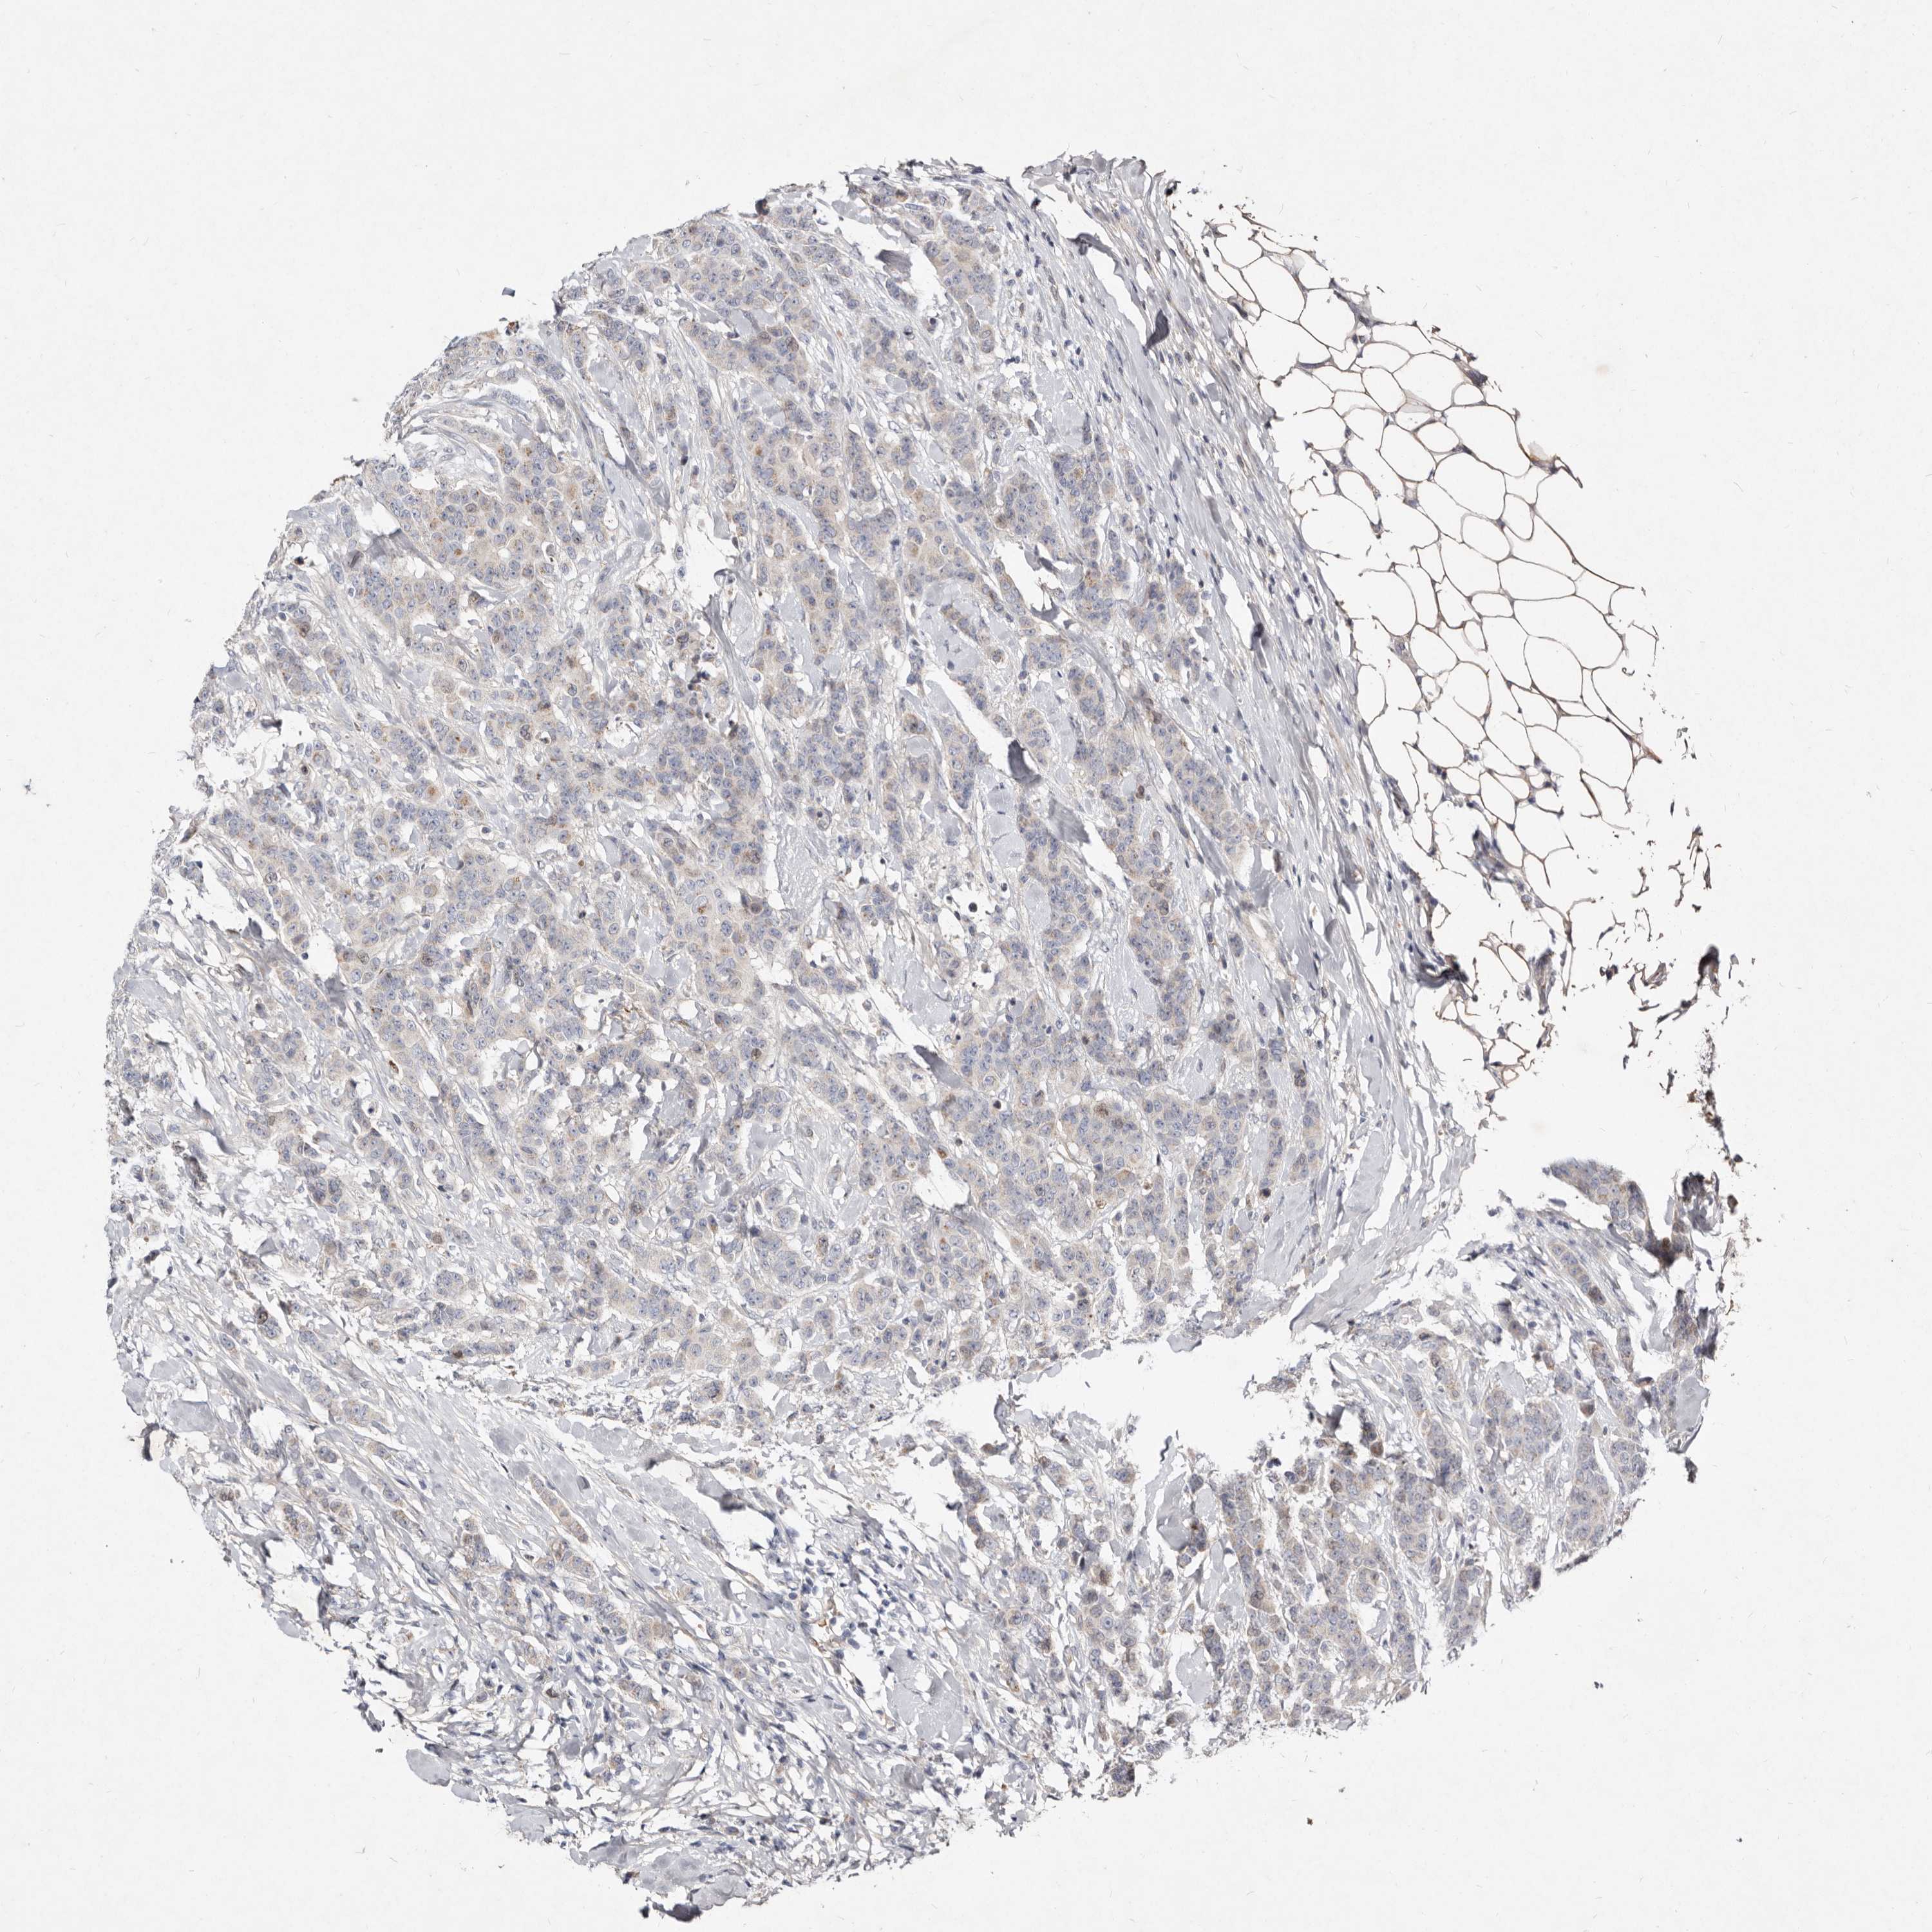

BRCA TCGA BRCA VALIDATION PROTEIN EXPRESSION

ANTIBODIES

AND

VALIDATION